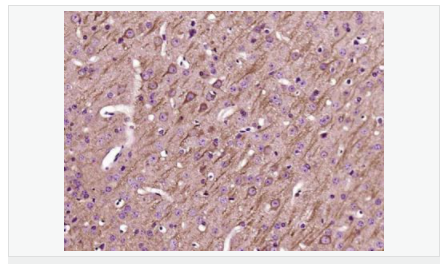

| 產品應用 | WB=1:500-2000 IHC-P=1:100-500 IHC-F=1:100-500 IF=1:100-500 (石蠟切片需做抗原修復) not yet tested in other applications. optimal dilutions/concentrations should be determined by the end user. |